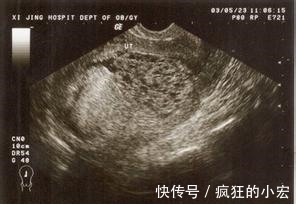

到了医院医生给做了检查,然后告诉刘芳一个消息,她没有怀孕,这对刘芳可是一个不小的打击,公婆当时就傻了,没办法接受这么一个结果。

没怀孕,肚子怎么会这么漂亮,之后医生告诉刘芳子宫内没有胎儿,而是有大量的气泡,这是葡萄胎,胎儿没有正常的发育,还好发现的早,要动手术排空子宫,不然会有生命危险。听到这个消息不禁让人崩溃恐惧。

葡萄胎:指妊娠后胎盘绒毛滋养细胞增生,间质高度水肿,形成大小不一的水泡,水泡间相连成串,形状就像葡萄一样。和怀孕的症状非常之相似。